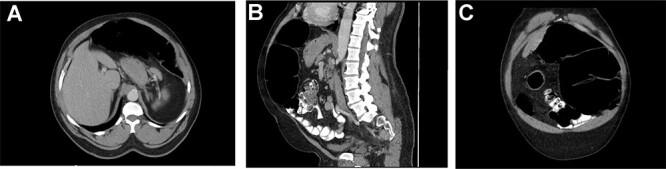

Colonic volvulus, where the colon twists around its mesentery, commonly occurs in the sigmoid and cecum. However, colonic volvulus of the splenic flexure is quite rare. Reported cases are limited but suggest that prolonged constipation in patients with either congenital anomalies, history of prior abdominal surgery, and or psychiatric history are described as common risk factors for large bowel volvulus. Here, we discuss a case of a 56-year-old man with a history of chronic constipation and no previous abdominal surgeries who presented to the emergency department with abdominal pain and distention. Further workup including a computed tomography imaging and decompressive via limited colonoscopy confirmed diagnosis of colonic volvulus of the splenic flexure. Surgical management of colonic volvulus is patient specific but invariably involves partial colectomy, as was performed in this case.

结肠扭转是指结肠围绕其肠系膜扭转,常见于乙状结肠和盲肠。然而,脾曲结肠扭转相当罕见。报道的病例有限,但提示先天性异常、既往腹部手术史或精神病史患者长期便秘被描述为大肠扭转的常见危险因素。在此,我们讨论一例56岁男性病例,该患者有慢性便秘史,既往无腹部手术史,因腹痛和腹胀就诊于急诊科。进一步检查包括计算机断层扫描成像和通过有限结肠镜减压,确诊为脾曲结肠扭转。结肠扭转的手术治疗因患者而异,但通常包括部分结肠切除术,本病例即如此。